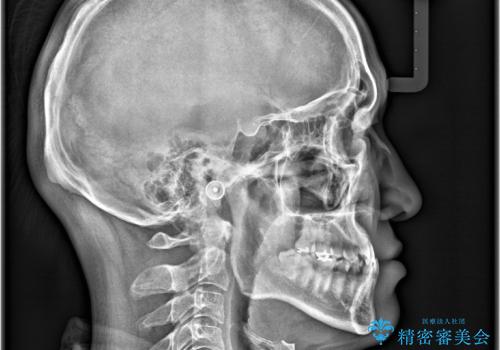

- 主訴:噛み合わせが反対になっているのを治したい

反対咬合と叢生改善のため、上下左右4番目の歯を抜歯し、審美装置にて矯正治療を行いました。

骨格性Ⅲ級を示しましたが、構成咬合位がとれたことから反対咬合と叢生改善のため、上下左右第一小臼歯を抜歯しワイヤー矯正を行いました。途中、バイトアップを行っています。